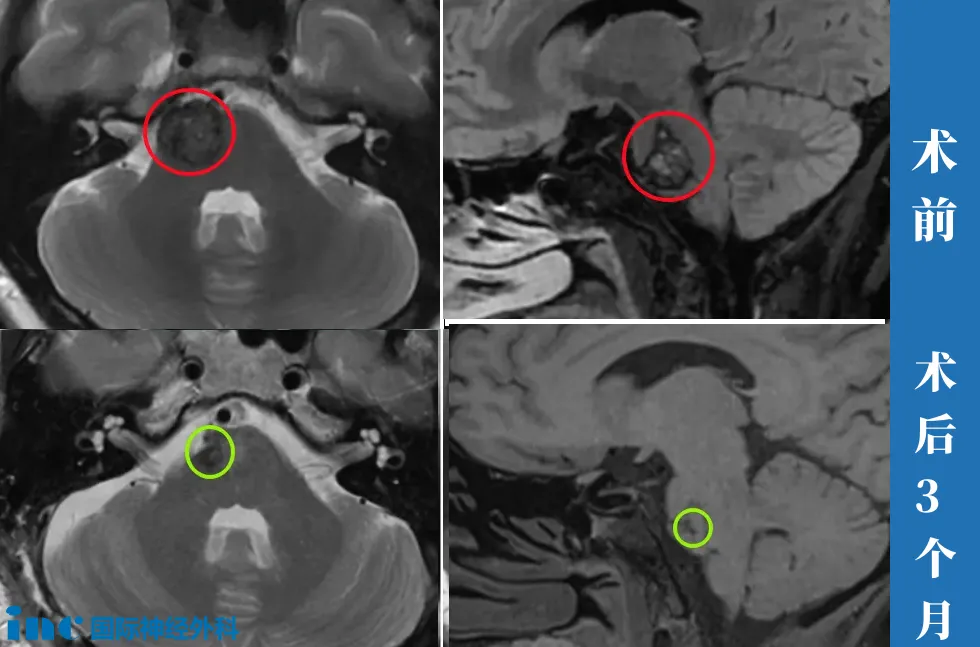

37岁女性—脑干海绵状血管瘤

“我就想我说我不想一辈子都是要保守,我说我想做,香港的医生不建议做。他说我这个地方风险很大,如果你准备好心态,如果做了有偏瘫、面瘫,你能接受就可以做,我肯定不敢。

手术做完一件事就是手脚、眼睛、摸一下那个脸,都没事,就觉得真的太神奇了巴教授。现在我觉得很好,四肢完全正常。听力也很好,眼睛、复视什么都没有,走路那些也挺好的。

▼行走自如,步伐自信而坚定,面部活动自如。

“当时国内的医生跟我说,你要是58岁你可以做手术,68了你还做啥手术?给你做瘫了,你躺在床上两年,你就完蛋了。

您看我这个状态多好,我前天做的手术。我刚才还跟儿子说,到今天终于有了我这个瘤子被摘除了的那种很真实的感觉。我一会儿要好好看看巴教授的手,有力量的上帝之手,真的被上帝吻过的手。太开心了,终于就没有负担了,不焦虑了。我现在下床完全没有问题。”

▼术后2天,柯女士行走自如,神采奕奕,和常人无异。